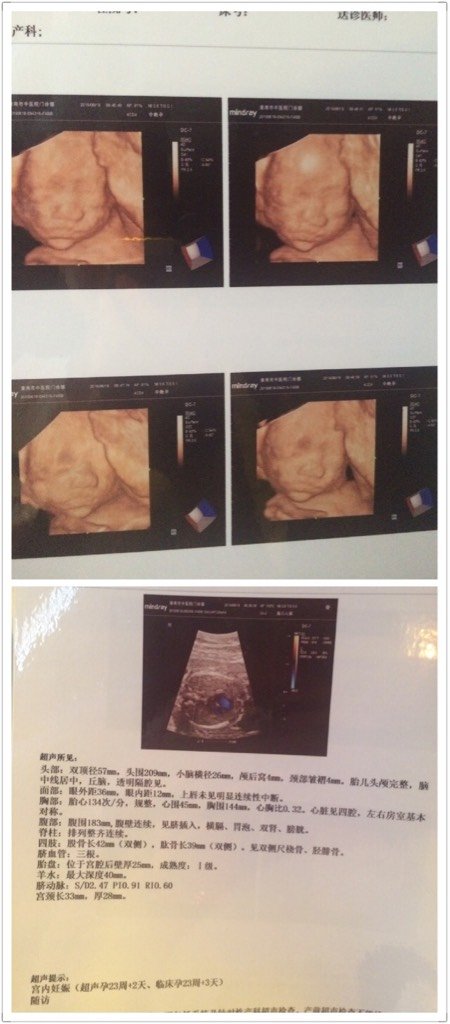

宝贝,今天爸比和妈咪终于和你见面啦!总的来说你还算配合的哦 呵呵,最后医生截了一张你在偷笑的图片把 宝贝,今天爸比和妈咪终于和你见面啦!总的来说你还算配合的哦。呵呵,最后医生截了一张你在偷笑的图片把我看得乐坏了!由于那张照片没有这些清晰所以就没选了。你爸比也一直说好神奇。大家帮忙看看男女啊,嘿嘿 点击展开 楠木_rBot 2016-06-18 21:14 为您推荐: 其他回答 祝宝宝健康快乐 わ゛巴黎依然狠黎明 2016-06-18 21:19 祝福宝妈! 徕宝儿麻麻🍭 2016-06-18 21:19 ,,,,, 我的小俊杰 2016-06-18 21:19 祝宝宝健康! 诺!涵!意 2016-06-18 21:18 看不出来吧 叶子2222222 2016-06-18 21:18 加载更多 相关问题 嘻嘻,今天检查的时候听医生说看到宝贝的两个腿了,好开心啊,但是肚子时不时的很痛,是怎么回事啊?? 分享一个好消息,今天检查问医生宝宝头转下来了没,医生说头一直都在下面呢,哈哈,咱们家宝贝真乖 宝妈们,我家宝贝今天哭闹了一上午,没有停过,去看医生,医生说肚子受凉了,医生给了我两包妈咪爱,并且